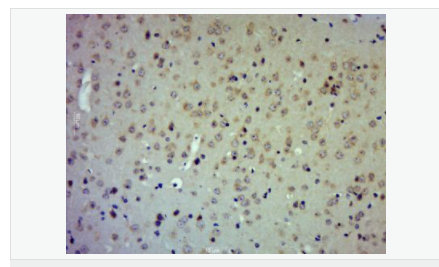

| 產(chǎn)品應(yīng)用 | WB=1:500-2000 IHC-P=1:100-500 IHC-F=1:100-500 ICC=1:100-500 IF=1:100-500 (石蠟切片需做抗原修復(fù)) not yet tested in other applications. optimal dilutions/concentrations should be determined by the end user. |